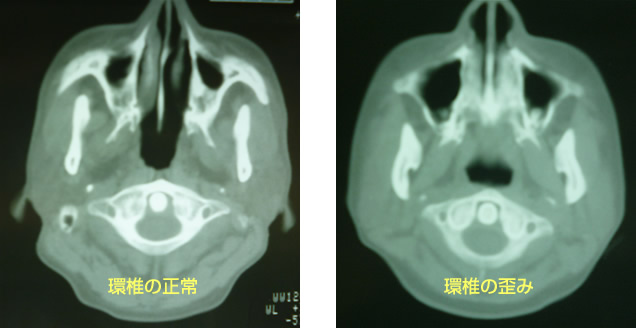

近年驚くほど首の痛み、ストレートネックで悩む人が増えてきています。 それはうつむく姿勢と肩を丸めて猫背姿勢になる為に前胸部『前頚部』の萎縮が考えられます。 ストレートネックの施術は前頚部の伸展ストレッチに重点を置いています。 頭部と首の境目、環椎その下を軸椎といいます。ストレスが影響でその首の関節が歪むと血管神経にまで影響が出ます。 又、後頭骨直下の神経によって後頭神経痛を引き起こします。

上記は脳外科医と共に症例発表研究の環椎CT撮影画像です。

以上の様々な首こりから不定愁訴を断つのは後頭骨直下(環軸関節)筋肉頭斜筋、後頭直筋、頭板状筋等の筋肉群を緩める、ストレスを与えている環軸関節の歪みを正常にもどす事にあると確信しています。